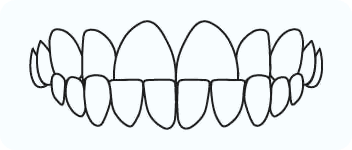

Crowding

Spacing

Rotations

A condition where one or more teeth are not aligned properly in relation to the adjacent and opposing teeth.